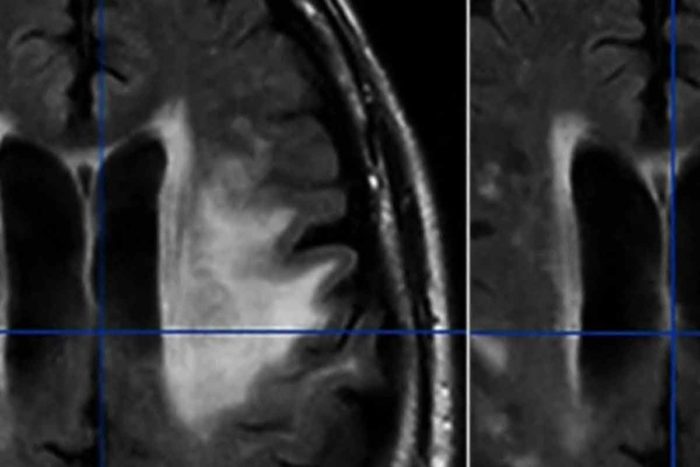

Breaking down brain barriers to fight cancer